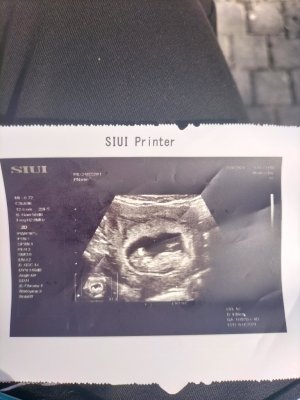

Nub teorisine göre cinsiyet tahmini yapabilen var mııı

Kafa yapısı erkek gibi canım sağlıkla gelsin

Yaaa kız istiyoduk da inşallah sağlıklı hayırlı hangisiyse o olsun inşallahKafa yapısı erkek gibi canım sağlıkla gelsin

Bizde 12 haftalık bizede tahminde bulunurmusunuzKafa yapısı erkek gibi canım sağlıkla gelsin

Tam bi kız gibi maşallah sağlıkla kucağınıza alınBizde 12 haftalık bizede tahminde bulunurmusunuz

Nub düzmü yaaa inşallah iki oğlum var sağlıklı olsun kız olsun istiyoruzTam bi kız gibi maşallah sağlıkla kucağınıza alın

Evet düz bir çıkıntı var kız gibi duruyo bana öyle geldi gönlünüzce olsun inşallahNub düzmü yaaa inşallah iki oğlum var sağlıklı olsun kız olsun istiyoruz

Benimkini de yorumlar mısınız 12+2 haftalık ultrason kağıdımEvet düz bir çıkıntı var kız gibi duruyo bana öyle geldi gönlünüzce olsun inşallah

Büyük ihtimal erkekBenimkini de yorumlar mısınız 12+2 haftalık ultrason kağıdım

Gönlümden erkek geçiyor ama kız olsa asla üzülmem henüz ikiside yok çünkü ilk bebeğim olcak sağlıkla gelsin inşallahBüyük ihtimal erkek

Bakın burdaki görsel ile kendi ultrasonumi kıyaslayınca kanısına varmıştım benBüyük ihtimal erkek

Buda bugünkü görüntümüz. Aslinda 13+1 adet tarihine göre ama Dr ult. 12+2 ddi bugün burda da erkek gibi sanki. cinsiyet hakkında bişey söylemedi bı ay sonra söylermişBende öyle vardım zaten çoğu tutuyo

Evet canım benimde böyle erkek olunca önden gidiyo zaten hayırlısı olsunBuda bugünkü görüntümüz. Aslinda 13+1 adet tarihine göre ama Dr ult. 12+2 ddi bugün burda da erkek gibi sanki. cinsiyet hakkında bişey söylemedi bı ay sonra söylermiş

Selam bizede bakarmısınız 13haftalık ama 2gün önde şuanKafa yapısı erkek gibi canım sağlıkla gelsin

Kıza benziyor 6 7 haftalık var mı fotoSelam bizede bakarmısınız 13haftalık ama 2gün önde şuan